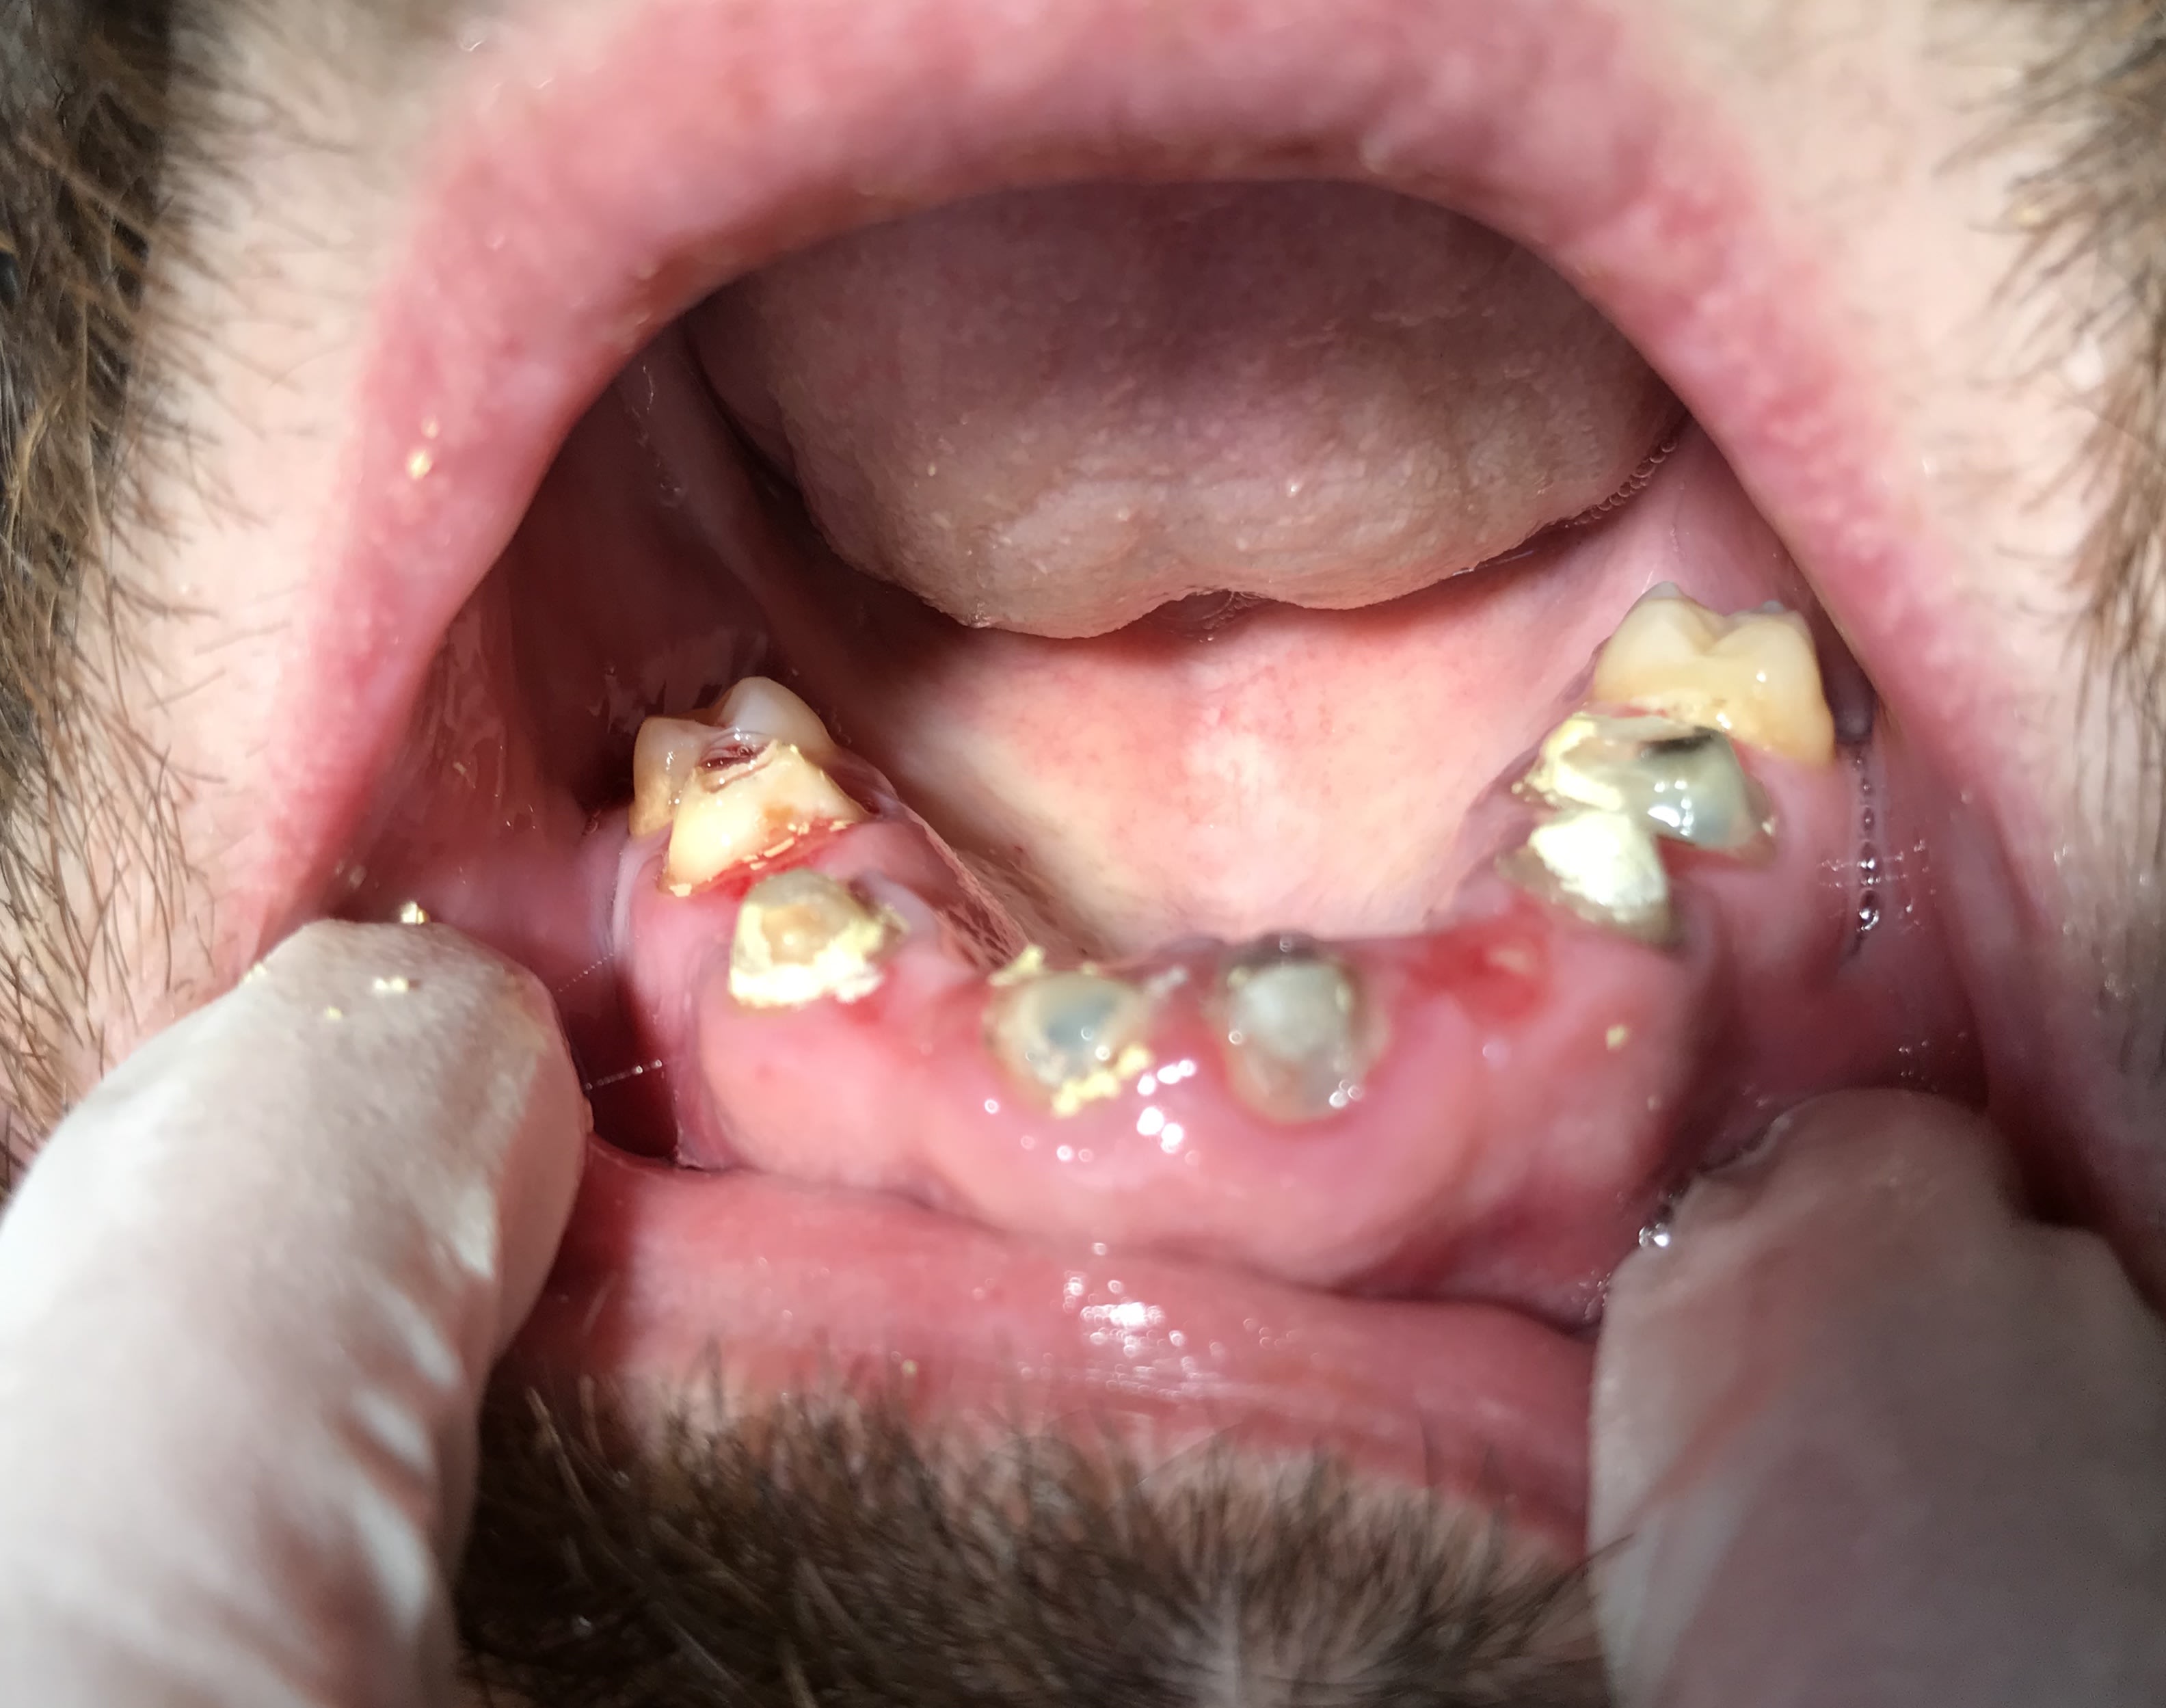

Il est où lachmar ? Cas qui a été traité par une roumaine. Il y avait un bridge que j’ai démonté avec une merde sous chaque dent.

J’ai essayé de conserver et retraiter 11 et 21 , j’attends que ça cicatrise. À la mandibule c’est pareil y a 4 dents manquantes. Plan de traitement 1 implant par dent manquante. Et chaque dents en bouche à retraiter.

La question est la suivante : est ce que je tente la conservation de la 6 avec le lentulo cassé ou je ne me casse pas le tronc et j’extrais ? As tu réussi à conserver des dents avec un lentulo cassé au delà de l’apex ?

Enlaye va rappliquer avec son extraction implantation immédiate :) , je ne peux pas le faire car le patient a déjà eu suffisamment de merdes en bouche. Faudrait pas rajouter une boulette de plus au tableau.

Photo bridge démonté

11 21 avant traitement

11 21 juste après retraitement

Radio de la 6 avec le lentulo

> Photo bridge démonté

> 11 21 avant traitement

> 11 21 juste après retraitement

> Radio de la 6 avec le lentulo

cher junior

ce cas aurait pu être traité par n'importe quel dentiste malhonnete

pour le lentulo chirurgie apicale et obturation retrograde